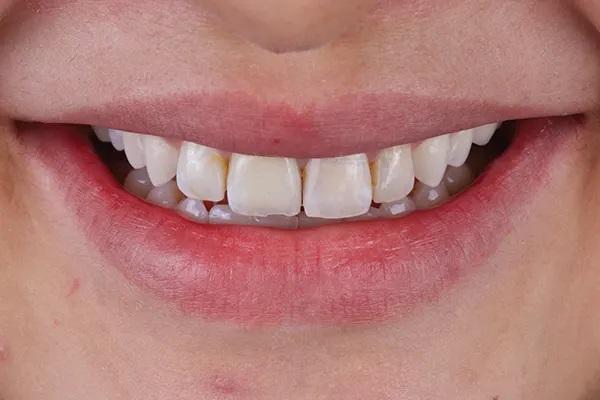

Пациентка 33 лет обратилась с жалобами на дефект прямой реставрации в переднем отделе выполненной из специальной смолы, имеющаяся у нее конструкция с опорой на имплантаты также имела дефект, а именно скол керамики по режущему краю резца и соседние зубы аномального размера (Фото 1 - Фото 3). В ее истории болезни не было выявлено противопоказаний к стоматологическому лечению. В 2015 году для восстановления целостности зубного ряда ей был установлен имплантат в области зуба 1.1., и рентгенологическое исследование показало, что имплантат хорошо сросся с костью. Глубина зондирования пародонта и тканей, окружающих имплантат, составляла от 3 до 4 мм, без признаков активного воспаления. У пациентки был хороший уровень гигиены полости рта.